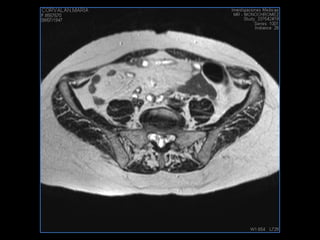

PROTOCOLO pancreas/ riñon AXIAL fat sat /AX in phase out phase AX T1 +SAG T2  COR T2, CON   GADOLINIO :  COR T1+AX T1(DIN) SAT: NO  FASE: RL THK: 4MM  COIL:  GAP: (FACTOR 1.4) 1MM FOV: 40 CM NEX:2 SINCRONIZACION RESPIRATORIA EN 3 O 4 CICLOS ALE